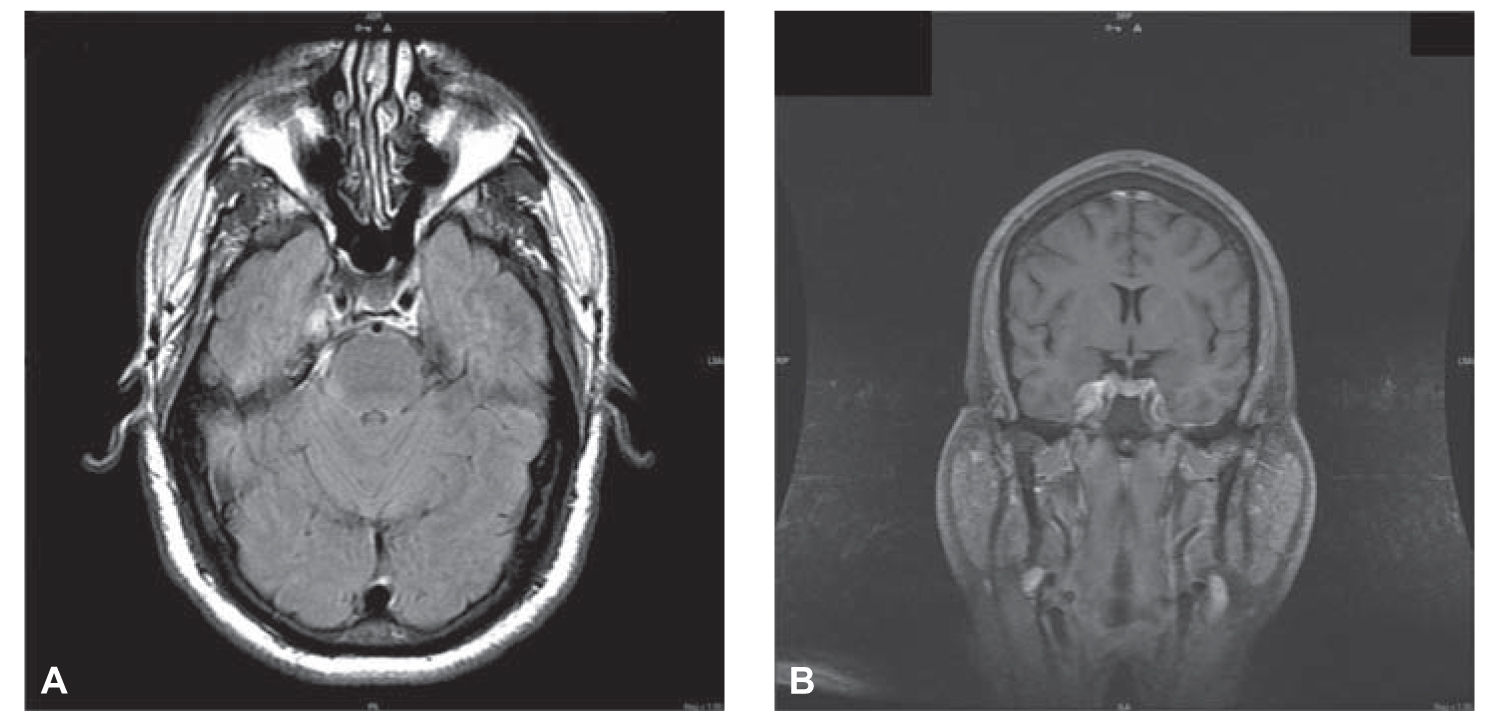

From www.researchgate.net

(PDF) Management of Unilateral Facial Numbness Labs For Facial Numbness Careful clinical and electrodiagnostic assessment, with attention to the pattern of involvement and the types of nerve fibers most affected,. Download a list of the blood tests that massachusetts general. Bell's palsy is a peripheral palsy of the facial nerve that results in muscle weakness on one side of the face. The recommended drug treatment consists of prednisolone 25 mg. Labs For Facial Numbness.